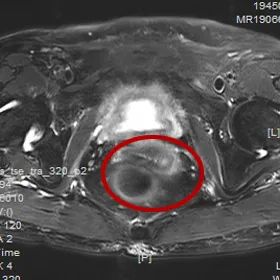

2個月后

被精心照顧的樊阿姨

不僅生活質(zhì)量有所提高

再次復(fù)查MRI影像

發(fā)現(xiàn)宮頸菜花樣腫物沒有了

這讓她非常激動